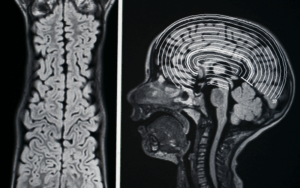

Media Gallary